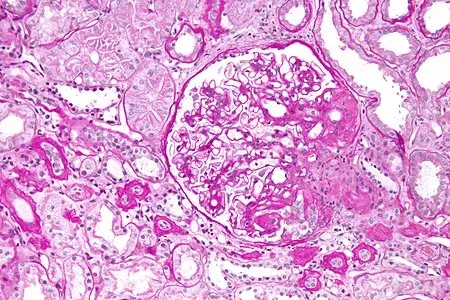

Nefropatia Membranosa: e se o paciente não responder ao tratamento inicial?

Nefropatia Membranosa: e se o paciente não responder ao tratamento inicial?

Neste vídeo, abordamos estratégias para lidar com pacientes com nefropatia membranosa que não respondem ao tratamento inicial. Ele enfatiza a importância da reavaliação constante e do ajuste do regime de tratamento com base nos resultados e no estado do paciente.

Como fazer o tratamento da Nefropatia Membranosa de forma prática!

Como fazer o tratamento da Nefropatia Membranosa de forma prática!